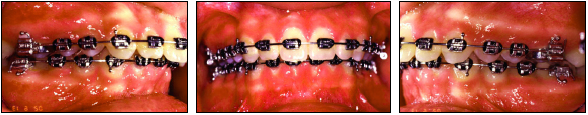

Alignment was carried out on light nickel titanium archwires. Wire sizes were progressively increased to .019" × .025" stainless steel in the maxillary arch and .021" × .025" stainless steel in the mandibular arch (Fig. 3, Fig. 9). The heavy stainless steel archwires were needed to avoid deflection after insertion of the TFBC. Both the maxillary and mandibular archwires were cinched distal to the first molars to prevent space opening and flaring, and to allow both arches to move as complete dental units.

Fig. 3 Case 1. After eight months of treatment, patient shows full-cusp Class II molar and canine relationships and 80% deep bite. Maxillary .019" × .025" and mandibular .021" × .025" stainless steel archwires are cinched distal to first molars.

Fig. 9 Case 2. After 10 months of treatment, patient is end-on Class II subdivision left, with mandibular midline deviating to left. Maxillary .019" × .025" and mandibular .021" × .025" stainless steel archwires are cinched distal to first molars.